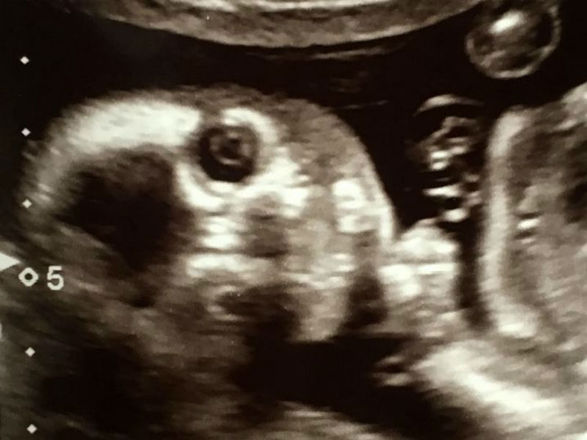

Uma mãe adolescente passou por situação semelhante no meio de um ultrassom. Ela viu o que parecia ser um "rosto alienígena" nas imagens. Veja a seguir!

A adolescente Sophie Scott, 16, de South Shields, na Inglaterra, ficou chocada ao encontrar uma "face alienígena" no ultrassom de seu bebê. As informações são do tabloide britânico Mirror

A mãe de primeira viagem, que está esperando o bebê com seu parceiro Stephen, 24, falou sobre o susto

"Fiquei com medo de o alien comer meu bebê", falou a jovem

"Nós vimos os olhos extras e aquela cabeça estranha atrás da criança". disse

"Eu tinha um ex-namorado que era fissurado em extraterrestres, acho que isso pode ser ele me perseguindo", brincou a garota

"Nós estamos brincando agora, mas eu realmente fiquei assustada já que ninguém conseguia identificar o que era aquilo", afirmou

O nascimento da criança é esperado para outubro e Sophie brincou com a proximidade da data com o Halloween

"Espero que ela não nasça no Halloween, isso seria assustador demais", concluiu